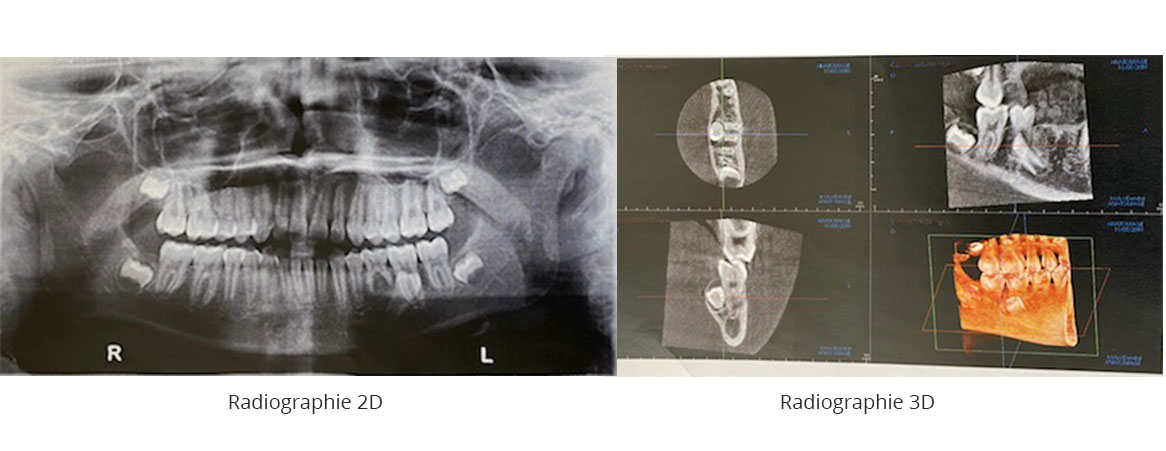

Quelques exemples

La quantité d’informations recueillies par ces radiographies est importante. Le Dr David peut y voir :

- les os de votre mâchoire ;

- votre dentition complète ;

- les chevauchements dentaires ;

- des pathologies pas toujours visibles en 2D ;

- la localisation de vos nerfs ;

- la densité de votre masse osseuse en préparation d’une chirurgie d’implants dentaires.

Pour ces raisons et d’autres encore,

la radiographie dentaire 3D est très efficace dans la planification d’une chirurgie implantaire, d’une extraction, d’une greffe osseuse et de toutes autres chirurgies de précision.